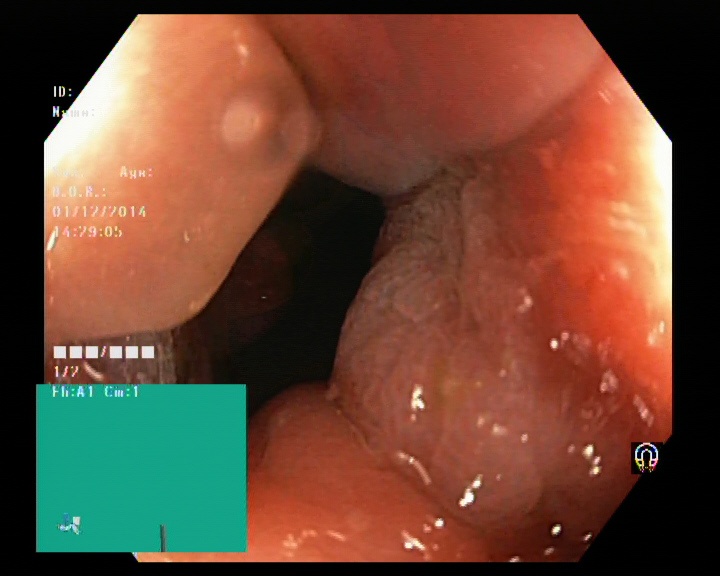

The Kvaris-SEG (Jha et al., 2020c) training dataset can be downloaded from https://datasets.simula.no/kvasir-seg/. It contains 1,000 polyp images and their corresponding ground truth mask as shown in Figure 1. The dataset was collected from real routine clinical examinations at Bærum Hospital in Norway by expert gastroenterologists. The resolution of images varies from to pixels. Some of the images contain a green thumbnail in the lower-left corner of the images showing the scope position marking from the ScopeGuide (Olympus) (see Figure 2). We annotate another separate dataset consisting of 160 new polyp images and use the resulting dataset as the test set to benchmark the participants’ approaches. Figure 2 shows some examples of test images used in the challenge.